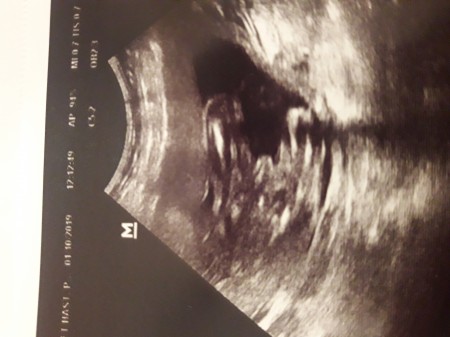

Merhaba bebeğimizin cinsiyeti ile ilgili ilk tahmini dr 11 haftada  erkek olarak yaptı, 16. hafta da ise yüzde 99 erkek dedi. fakat uygun pozisyon vermediğini de söyledi.ileriki ayda değişme ihtimali var mıdır ? Artık kesin gözüyle bakabilir miyiz ya da başka doktora gitmeye gerek var mıdır?

Gebelik haftası 16+0

sanırım alttan bacak arası görünümü değil mi bu bizde bu pozisyona baktığını görmedim ben

yandan yüzünü kapamış görüntü var

Evet bu bacak ortası canim

bende görüntü ekledi  soruya senin ki gibi net görünen birşey yok

Cinsiyet kismi yokki canim az daha bekle bence